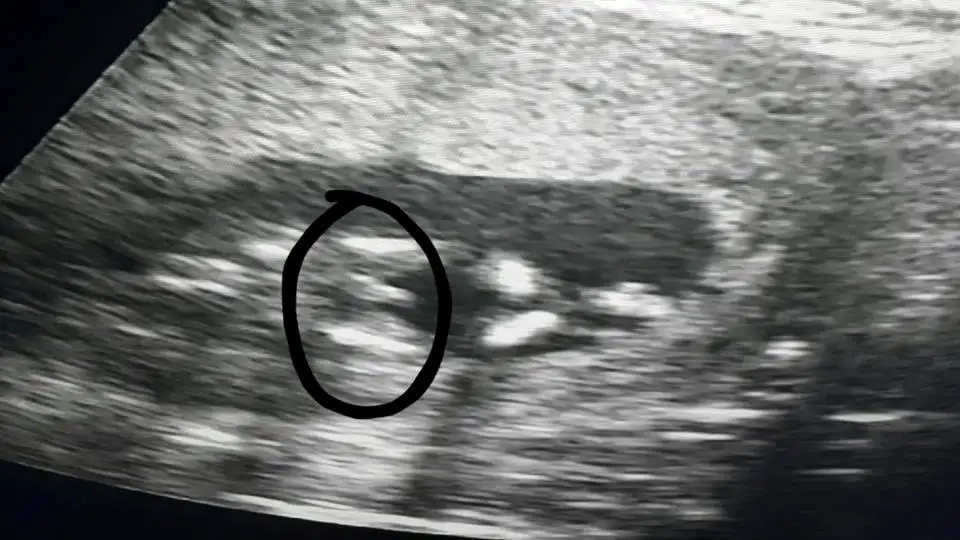

Pipiye benziyor canım, hayırlısı olsun.kızlar bebegıme doktor erkek dedı ama kesın deıl dedı bu resımde bacak arasının sızce

saol cnmPipiye benziyor canım, hayırlısı olsun.